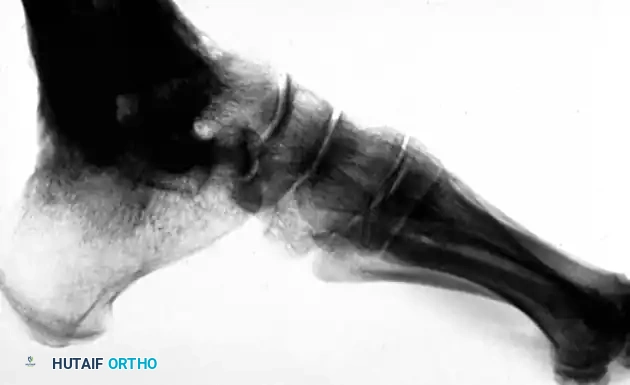

Image

FIGURE 88-42 A: Preoperative radiograph demonstrating a severe talar body fracture with an associated fibular fracture, a classic injury pattern that, if unsalvageable, may necessitate tibiocalcaneal arthrodesis.